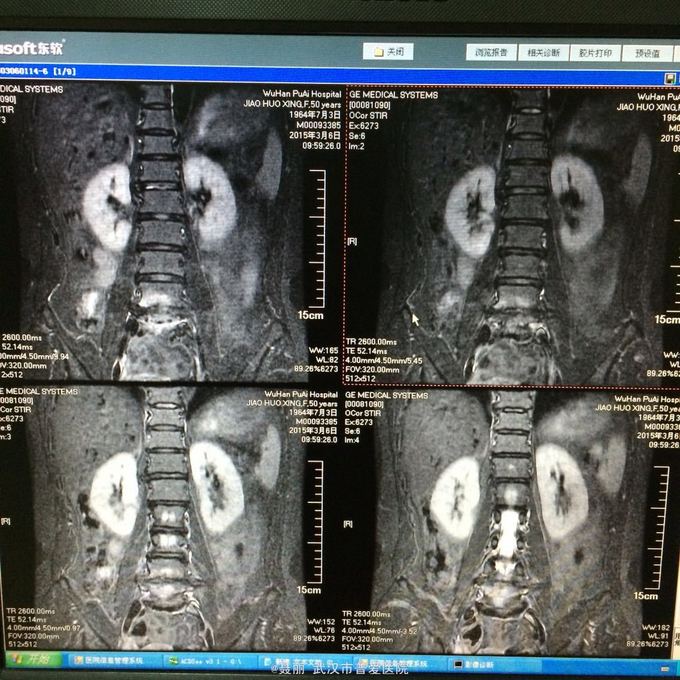

:L4/5棘突间轻压痛,叩痛,棘间左侧椎旁压痛;双下肢肌力、肌张力正常,病理反射未引出。 门诊资料:外院行腰椎CT检查示:L3-S1椎间盘膨出,L4椎弓崩裂并向前滑脱(重度)椎管狭窄。 入

入院诊断:、腰椎滑脱(L4/5 峡部裂性) 诊疗计划:1:完善有关检查2卧床休息,行改善微循环、3.腰椎后路复位减压植骨融合术

行改善微循环、3.腰椎后路复位减压植骨融合术 腰椎滑脱(L4/5 Ⅱ度)、腰椎管狭窄症(L3/4)、腰椎间盘突出症(L5/S1)查体双下肢感觉、活动无明显异常。双下肢末梢血液循环可。换药见伤口对合良好,无明显红肿渗出。伤口已拆线。嘱加强双下肢活动及功能锻炼,避免下肢深静脉血栓,主动及被动四肢活动,预防血静脉及床褥形成,加强腰背肌锻炼,适量康复功能锻炼。一个月后来复查伤口愈合好,疼痛没有,活动可